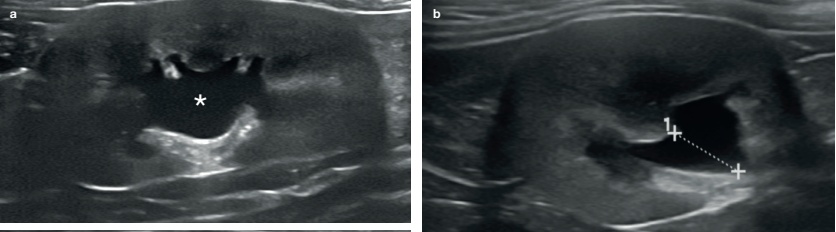

심한 수신증의 경우, 압력으로 인한 신장 실질의 괴사로 조직 손실이 상당히 발생할 수 있습니다. 극단적인 경우, 현저히 확장된 신우를 둘러싸는 얇은 테두리 조직만 남을 수도 있습니다(그림 3). 또한 신문(hilum)에서 신장 피막 쪽으로 뻗는 여러 개의 고에코성 선형 띠가 보일 수 있는데, 이는 신우 사이 격막(interdiverticular septa)을 나타냅니다(그림 3c).